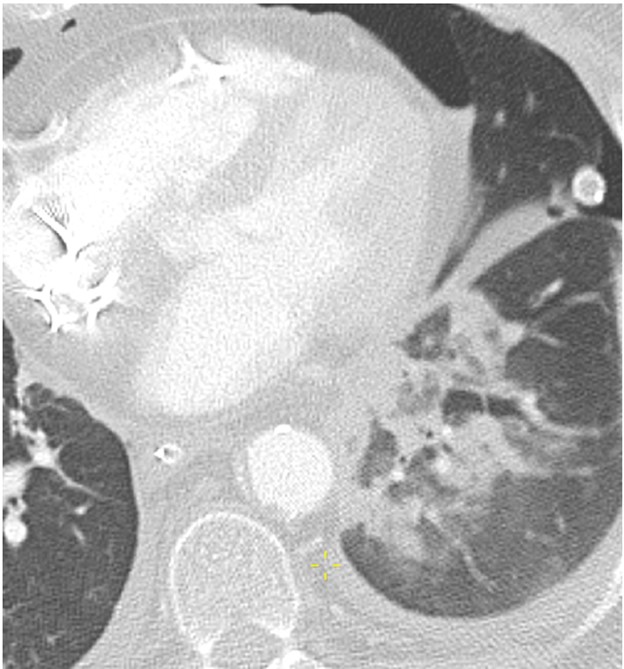

Hemothorax, the presence of blood products in the pleural space, should be suspected if there is rapid increase in the volume of pleural fluid over serial imaging or if pleural fluid is hyperattenuating relative to simple fluid on CT. Hemothorax can be heterogeneous in attenuation on CT due to mixing or layering of new blood products with old blood products; a fluid-fluid level may be present. Figure 5 (left) shows a patient with hemothorax.

Empyema, the presence of infected material (i.e., pus) in the pleural space, should be suspected if there is persistence of pleural fluid over serial imaging for more than 1 week or so after transplant and if visceral and parietal pleural thickening or loculated pleural fluid is present on chest CT. On contrast-enhanced CT of the chest, patients with empyema may have abnormal thickening and enhancement of the visceral pleura and parietal pleura with fluid between the two pleural layers, which is known as the split pleura sign. Figure 5 (right) shows a patient with empyema.